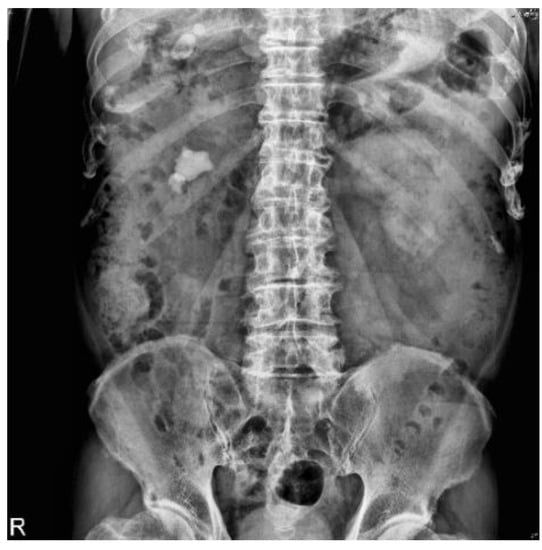

2.2. Datasets

3.4. Subsystem 2—Segmentation Model for Medical Images